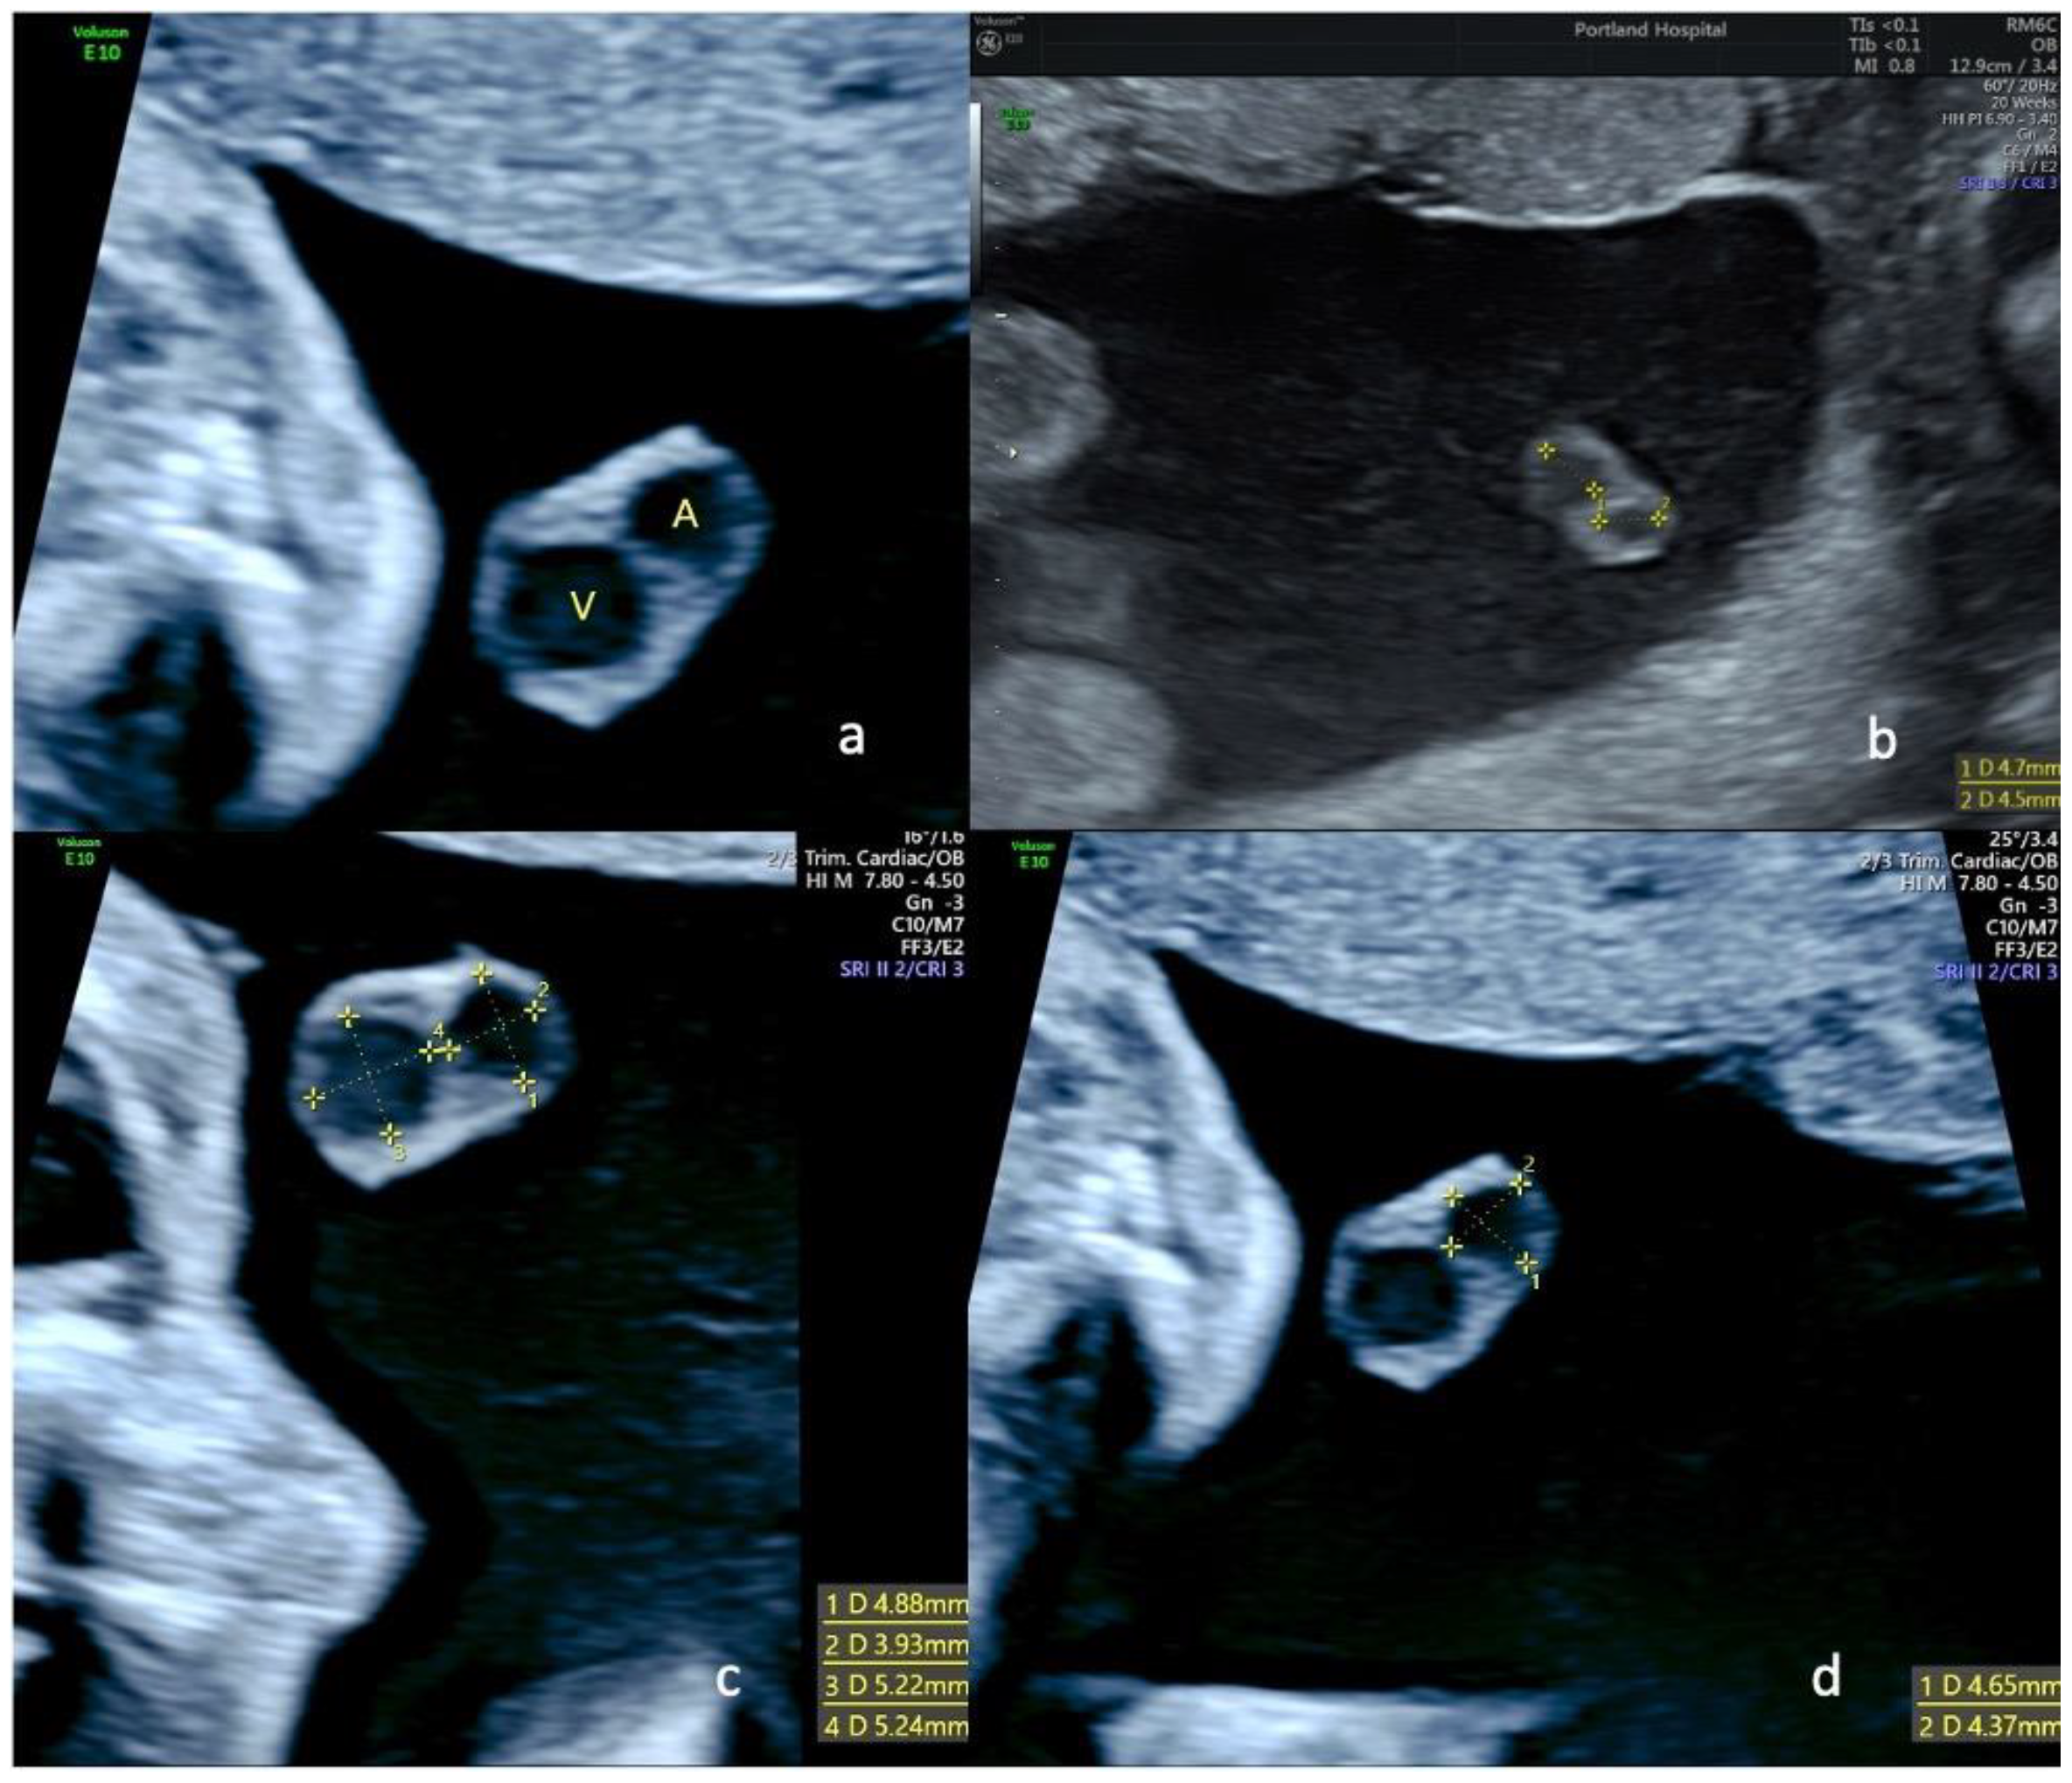

Figure 2.

Ultrasound views of the free portion of the umbilical cord in a fetus with single umbilical artery at 22 weeks of gestation; (a) transverse view of the free loop showing the remaining artery (A) and the umbilical vein (V); in pictures (b–d), we can see different measurements of arteries and veins in a transverse view of a free loop of umbilical cord at 22 weeks in fetuses with SUA.